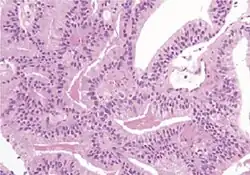

Intraductal carcinoma

Intraductal carcinoma of the prostate gland (IDCP), which is now categorised as a distinct entity by WHO 2016, includes two biologically distinct diseases. IDCP associated with invasive carcinoma (IDCP-inv) generally represents a growth pattern of invasive prostatic adenocarcinoma while the rarely encountered pure IDCP is a precursor of prostate cancer.[20] The diagnostic criterion of nuclear size at least 6 times normal is ambiguous as size could refer to either nuclear area or diameter. If area, then this criterion could be re-defined as nuclear diameter at least three times normal as it is difficult to visually compare area of nuclei.[20] It is also unclear whether IDCP could also include tumors with ductal morphology.[20] There is no consensus whether pure IDCP in needle biopsies should be managed with re-biopsy or radical therapy. A pragmatic approach would be to recommend radical therapy only for extensive pure IDCP that is morphologically unequivocal for high-grade prostate cancer.[20] Active surveillance is not appropriate when low-grade invasive cancer is associated with IDCP, as such patients usually have unsampled high-grade prostatic adenocarcinoma.[20] It is generally recommended that IDCP component of IDCP-inv should be included in tumor extent but not grade.[20] However, there are good arguments in favor of grading IDCP associated with invasive cancer.[20] WHO 2016 recommends that IDCP should not be graded, but it is unclear whether this applies to both pure IDCP and IDCP-inv.[20]

Ductal adenocarcinoma may have a prominent cribriforming architecture, with glands appearing relatively round, and may thereby mimic intraductal adenocarcinoma, but can be distinguished by the following features:[10]

| Feature | Ductal adenocarcinoma | Intraductal adenocarcinoma |

|---|---|---|

| True fibrovascular cores in micropapillary architecture | Present | Usually absent |

| Cribriform lumens | Lined by pseudostratified, columnar cells | Punched out lumens lined by cuboidal cells |

| Basal cell markers | Usually negative | Usually positive |